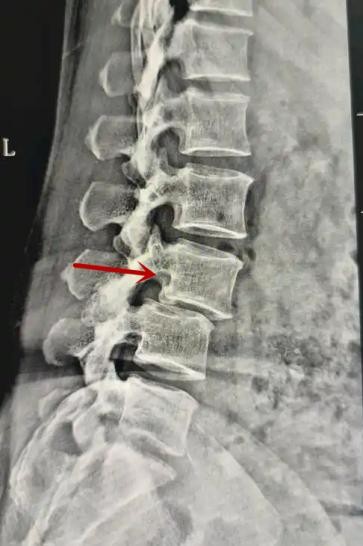

箭头提示腰1椎骨折

箭头提示腰3椎体滑脱